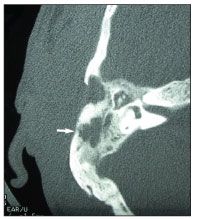

Figure 1.CT scan showing erosive changes of the right temporal bone and bony destruction in the temporal squamosa.

CT scans of the brain and temporal bones revealed focal collections in the subcutaneous tissue of the right temporal region and erosive changes of the right temporal bone with bony destruction in the temporal squamosa as well as in the mastoid portion (Figure 1). MRI angiography confirmed those findings and revealed a thrombosis of the right transverse and sigmoid sinuses. Cultures were obtained, and surgical debridement was scheduled.